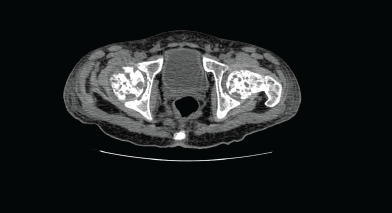

Computed tomography (CT) of the pelvis showed multiple lytic lesions involving the sacrum, bilateral iliac bones, acetabulum, head, neck, and the proximal shaft of both femurs with endosteal scalloping and cortical breaks suggestive of leukaemic infiltrates. Linear periosteal reaction could be visualised in bilateral metadiaphyseal region of femur.

Figure 2. Computed tomography (CT) of the pelvis showed multiple lytic lesions.

Radiology

Radiological changes in acute leukaemia include osteopenia, lytic and sclerotic lesions, transverse metaphyseal bands, intra-medullary osteolytic mottling, and periosteal new bone formation. These changes have been reported in 41–70% of children with ALL [14]. However, destructive bone involvement with hypercalcaemia as observed in our patient is uncommon. The prognostic implication of bone lesions in ALL is unclear.